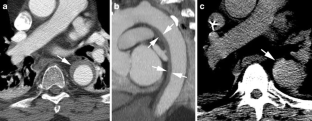

The aim of this study is to describe the frequency, computed tomographic angiography (CTA) imaging appearance, management, and outcome of patients who present with minimal thoracic aortic injury. This retrospective study was Institutional Review Board-approved. Eighty-one patients with blunt traumatic aortic injuries (BTAI) were identified between 2004 and 2008, comprising 23 patients with minimal aortic injury (MAI) (mean age, 43.2 years ±18.2 years; 12 males and 11 females) and 58 patients with non-minimal aortic injury (mean age, 42.6 years ±22.7 years). CTA imaging was reviewed for each patient to differentiate those with MAI from those with non-MAI BTAI. Inclusion criteria for MAI on CTA were: post-traumatic abnormality of the internal contour of the aorta wall projecting into the lumen, intimal flap, intraluminal filling defect, intramural hematoma, and no evidence of an abnormality to the external contour of the aorta. Relevant follow-up imaging for MAI patients was also reviewed for resolution, stability, or progression of the vascular injury. The electronic medical record of each patient was reviewed and mechanism of injury, injury severity score, associated injuries, type and date of management, outcome, and days from injury to last medical consultation. Minimal aortic injury represented 28.4 % of all BTAI over the study period. Mean injury severity score (37.1), age (43.2 years), and gender did not differ significantly between MAI and non-MAI types of BTAI. Most MAI occurred in the descending thoracic aorta (16/23, 69 %). Without operative or endovascular repair, there was no death or complication due to MAI. One death occurred secondary to MAI (4.4 %) in a patient who underwent endovascular repair and surgical bypass, compared with an overall mortality rate of 8.6 % in the non-MAI BTAI group (p = 0.508). The most common CT appearance of MAI was a rounded or triangular intra-luminal aortic filling detect (18/23 patients, 78 %). In a mean of 466 days of clinical follow-up, no complications were observed in survivors treated without endovascular repair or operation. Minimal aortic injury is identified by multi-detector row CT in more than a quarter of cases of BTAI and has a low mortality. Conservative management is associated with an excellent outcome.

Fig. 1

Fig. 2

Fig. 3

Fig. 4